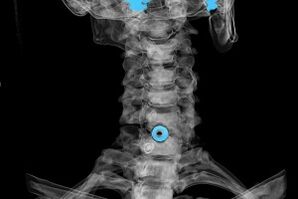

Le diagnostic est établi sur la base de symptômes caractéristiques, ainsi que à l'aide de :

- Rayons X. La méthode est inefficace, en particulier dans les derniers stades du développement de l'ostéochondrose.

- IRM (imagerie par résonance magnétique) de la colonne cervicale. Une méthode qui permet de visualiser les structures osseuses, les hernies discales intervertébrales, leur taille et leur direction de développement.

- Tomodensitométrie. Une solution moins efficace que l’IRM, puisque la présence et la taille des hernies sont difficiles à déterminer.